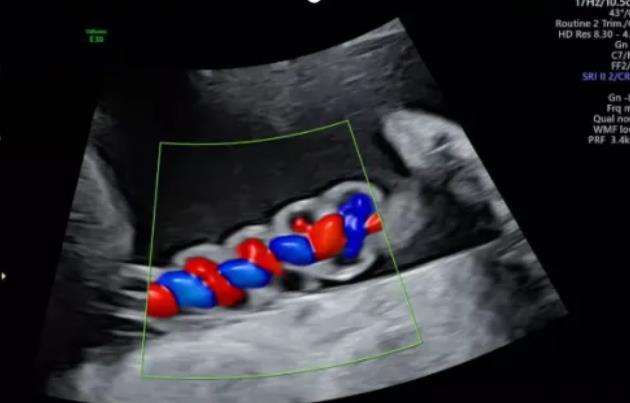

漯河市中醫(yī)院健康科普:超聲檢查之臍帶螺旋

聲像圖特征:臍動(dòng)脈表現(xiàn)為過度螺旋,臍血管變細(xì),縱切面呈“麻花狀”,橫切面呈“鼠眼狀”;

2、臍帶螺旋過松

聲像圖特征:胎兒臍帶縱切面示血管呈平行排列,螺旋稀少,彩色多普勒血流成像示臍帶血管內(nèi)充滿的紅藍(lán)血流呈平行排列,麻花狀螺旋消失。